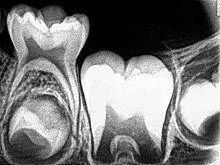

一般来说,牙齿的颜色是由牙釉质(牙冠部的外壳)的颜色和牙本质(牙齿的内部主体结构)的颜色共同决定的。因为牙釉质通常为白色且呈半透明状,而牙本质为淡黄色,所以牙齿最终的颜色取决于牙釉质的透明度及牙本质的颜色。如果牙本质颜色相同,牙釉质透明度越高,牙本质的颜色透出来就越多,牙齿看起来越黄;反之则越白。因此多数情况下,牙齿偏黄或偏白是可以反映其牙釉质透明度高低的。

图源:维基百科

牙釉质的透明度又取决于其钙化程度,即钙化程度越高,则透明度越高;反之则越低。所以正常情况下,牙齿偏黄或偏白也是可以反映牙釉质钙化程度高低的。当然有时是牙本质颜色改变导致的牙齿颜色改变,例如四环素牙等。